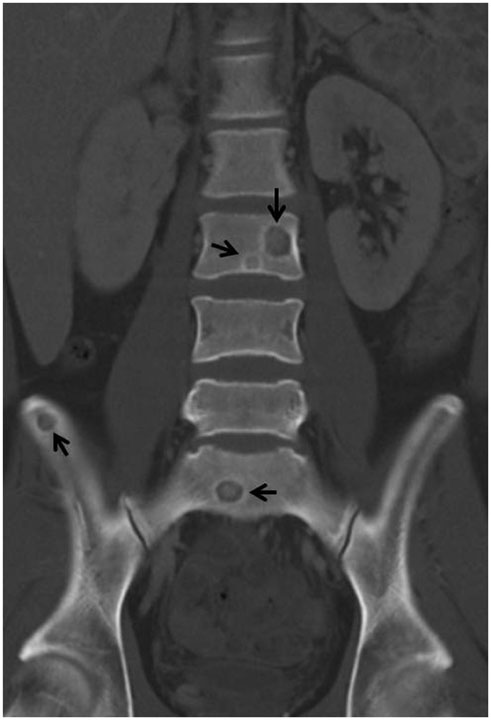

- The spine is the most common site of skeletal involvement in tuberculosis. The radiologic features are reportedly characterized by destruction of the vertebral body, subligamentous extension or subchondral penetration, frequent paravertebral abscess formation and late involvement of the disk space. We experienced a case of a 25-year-old male who was a human immunodeficiency virus carrier without antiretroviral therapy. Incidental findings on abdominal computed tomography included multiple well-demarcated and ovoid osteolytic lesions with hyperdense rims disseminated in the thoracic, lumbar, and sacrum vertebrae, as well as in both ilii. On the lumbar spine magnetic resonance imaging, multiple small round lesions of isointense signal intensity with peripheral hyperintense rims were found on both T1- and T2-weighted imaging. The lesions had peripheral rim enhancement on gadolinium-enhanced T1-weighted imaging. Based on our experience, this rare image finding is one of the manifestations of disseminated tuberculosis.